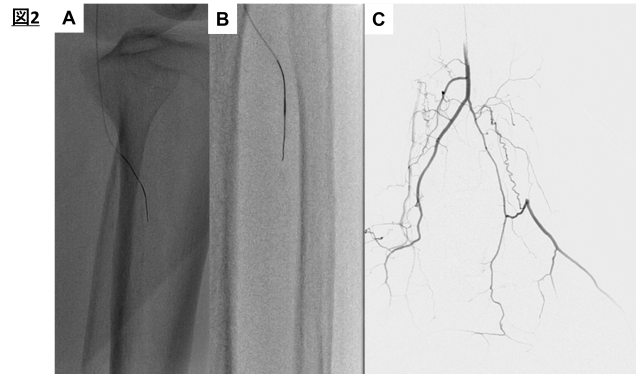

まずATAへの順行性ワイヤリングから開始した。VASSALLO GT 14 NS1( 以下NS1)によりATAを選択してマイクロカテーテルを進めた( 図2 A )。

C T O 入口部は固くN S 1 が進まなかったため、VASSALLO GT 14 NS3( 以下NS3)を使用して、CTO内への進入に成功した( 図2B)。

ATAはlong CTOでありここでtrans-collateralによる逆行性アプローチを追加した(図2C: PAからの先端造影)。